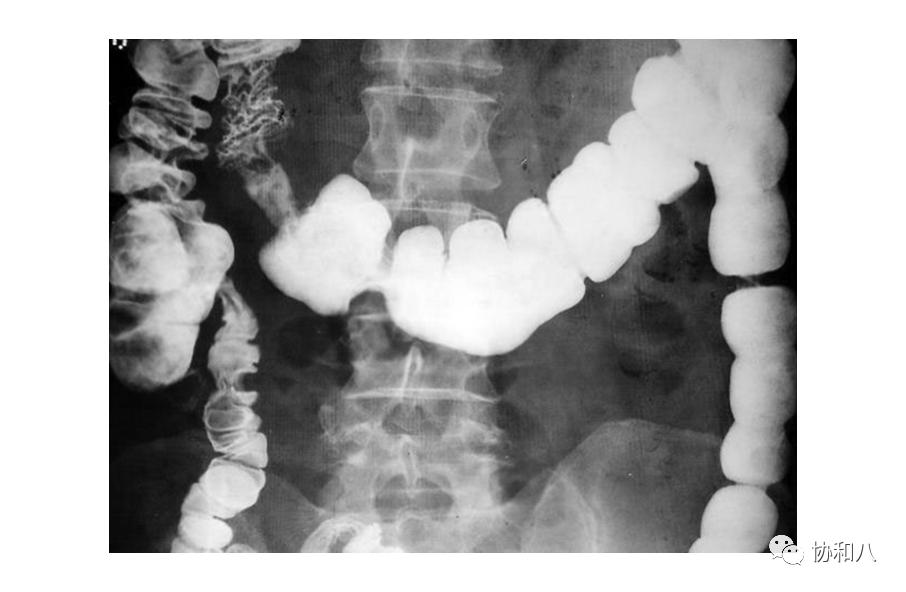

4. 葡萄串征:

常用于描述囊状支气管扩张(图1&2)的典型CT表现,也见于结肠含气囊肿(图3)。描述:簇状/串状囊腔呈葡萄串样。

左滑高能预警